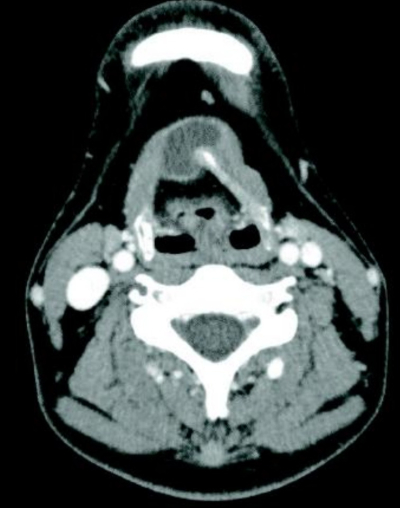

36歳の男性。前頸部腫瘤を主訴に来院した。2か月前に初めて自覚したが、その後、腫瘤の大きさに変化はない。前頸部傍正中の舌骨付近に半球状、単発の25×25mmの柔らかい腫瘤を触れる。嚥下時にこの腫瘤は挙上する。頸部造影CTを別に示す。

診断はどれか。

c. 正中頸嚢胞